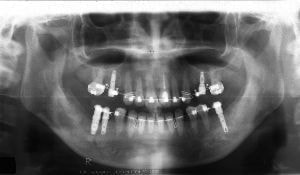

治療例1 (インプラント補綴+矯正)